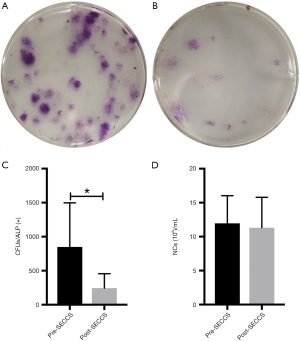

Replanted cell counting

For nucleated cell counting, the precipitate from 1 mL of pre- or post-SECCS-processed bone marrow after centrifugation was mixed with red blood cell lysate (TBD, China) to remove red blood cells, and the number of nucleated cells was counted by a counting machine (Countess II, Thermo Fisher, USA).

To count the number of MSCs, 1 mL of pre- or post-SECCS-processed bone marrow was diluted in the basic medium and seeded into six-well plates at a density of 0.1 mL/well. After 2 days of culturing, pro-osteogenic medium (α-MEM supplemented with 10% fetal bovine serum, 0.1 mM dexamethasone, 50 mM ascorbic acid, and 10 mM β-glycerophosphate sodium) was added and changed every 2 days at 37 °C with 5% CO2 for osteogenesis of the MSCs. Two weeks later, alkaline phosphatase staining was performed to count the number of CFU/ALP+ as the number of MSCs. In detail, after 20-minute fixation by 4% paraformaldehyde, the cultures were added with ALP stain (Shanghai Hongqiao, China) at 37 °C for 1 hour.

The replanted cell number was calculated according to the following formula:

N = Npre × Vpre − Npost × Vpost

where Npre and Npost represent the number of cells (including NCs and MSCs) per mL of bone marrow pre- and post-SECCS, respectively. Vpre and Vpost stand for the total volume of bone marrow pre- and post-SECCS, respectively.

After treatment with SECCS, the number of CFU/ALP+ in the goat bone marrow decreased significantly (t=3.078; P=0.037) from 848.3±649.2 per mL to 244.0±212.6 per mL (Figure 5A,B,C). There was no significant difference in the decrease of bone marrow nucleated cells (t=1.977, P=0.119) from 11.9±4.1×106 to 11.3±4.5×106 per mL (Figure 5D). In this study, the average number of replanted MSCs for each goat in the MSCs/β-TCP–filled group was approximately 31,321.7±22,554.7.